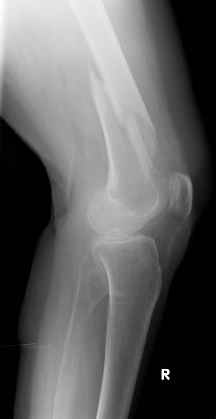

Ортопедия и травматология Отправлено Waldemar Kindsvater 09 Апрель 2005, 00:39

Уважаемые коллеги, Было бы интересно узнать вашу тактику при остеосинтезе этого перелома.

Видно спиральный перелом дистального метадиафиза бедра. У нас бы сделали антеградный закрытый интрамедуллярный остеосинтез.